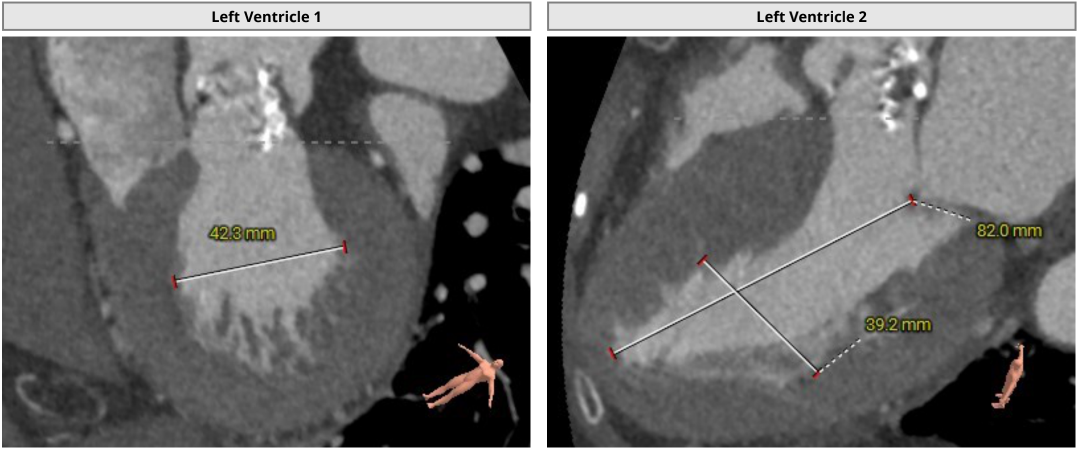

3.瓦氏窦、窦管交界内径正常,升主动脉扩张;左室腔内径可,心室壁增厚;

脉阻挡风险、左室大小及横位心评估

3.左室腔内径可,心室壁增厚,术中密切关注血流动力学变化;

随着TAVR技术在国内的普及,主动脉瓣狭窄患者有了更多的治疗选择。本例患者为主动脉瓣重度狭窄伴轻度反流,患者伴代偿性心力衰竭,术前评估适宜行TAVR手术,有TAVR手术指征。术前CT分析提示患者为Type0型二叶式主动脉瓣,瓣环径23.5mm,瓣叶增厚伴重度钙化,钙化主要分布于无窦与左窦交合缘及瓣叶边缘,LVOT呈类直筒状形态,预估人工瓣膜会有较明显形变,有根部撕裂、损伤风险。左室流出道可提供辅助锚定,综合预估瓣膜锚定定位精度要求较高。患者又为横位心,主动脉弓距及夹角尚可,升主动脉扩张,需警惕血管夹层、破裂等风险,对经导管主动脉瓣输送系统过弓、跨瓣的性能要求较高。综合以上因素,该患者行TAVR手术对术者快速、精准的操作能力及手术团队的密切配合要求较高。广东省人民医院赣州医院(赣州市立医院)倪忠涵院长带领团队,经过心内科、心外科、麻醉科、超声等多学科团队的缜密讨论,最终决定为患者施行TAVR手术治疗。